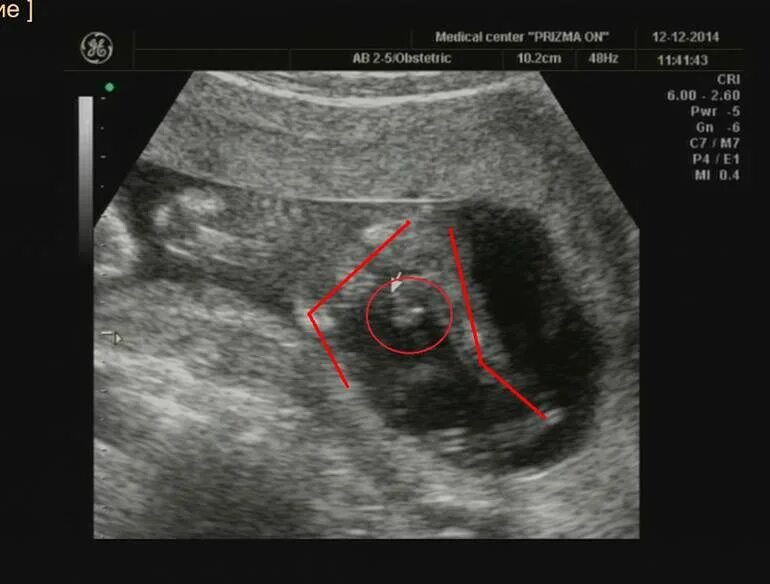

Может ли узи ошибиться в поле